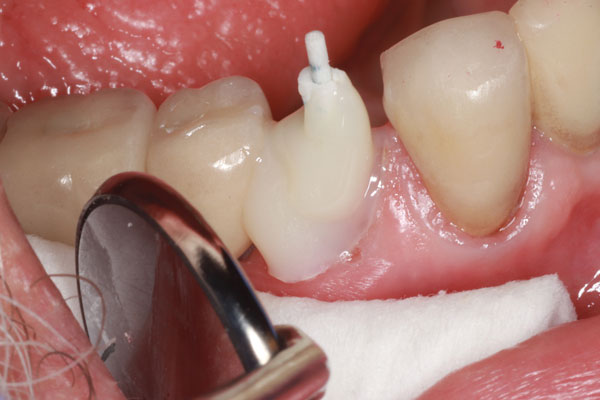

Un cemento de resina de curado dual / material de acumulación (Core-Flo DC Lite, BISCO) se mezcló y se colocó primero en el poste y la manga. A continuación, se colocó una pequeña cantidad de cemento en el canal y se insertaron rápidamente el poste y el manguito. El poste se empujó firmemente hacia abajo en el canal y se sujetó mientras se empujaba la manga hacia abajo con un par de pinzas de algodón. Luego se colocó resina adicional para rellenar y acumular hasta el nivel deseado, y se mantuvo una luz de curado sobre el aspecto oclusal durante 40 segundos (Figura 6). Después de que el área se aisló de la humedad y se dejó fraguar por completo durante 3 minutos, se tomó una radiografía del poste y el manguito con la acumulación (Figura 7), se realizó una preparación de la corona (Figura 8) y se fabricó un provisional para el paciente (Figura 9). Regresó 3 semanas después para que se asentara la corona final (Figura 10).

Imagen 8. Vista bucal de la preparación completa de la corona.